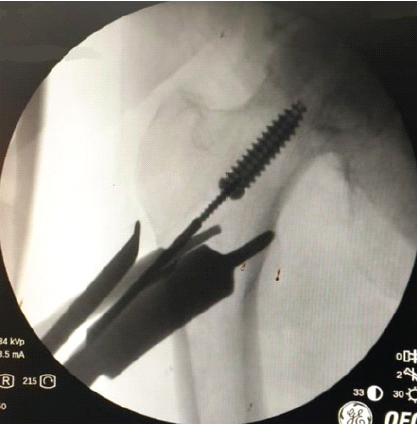

The next method that was attempted, as shown in Fig. 4 was to thread a thin 2.5 mm Schanz pin into the canal of the interference screw and pull it back.

Figure 4: Attempting removal with a Schanz pin.

This proved to be partially successful, and the screw was pulled back a certain distance. Following this, the Schanz pin was passed into the screw head and the threads of the Schanz pin engaged with the head of the screw and thus, the screw could be pulled out without the need for additional exposure, enlargement of the reaming track, or creation of a bone window (Fig. 5) [8]. The procedure was then completed and repeated on the contralateral side without complications.

Figure 5: Screw successfully removed.